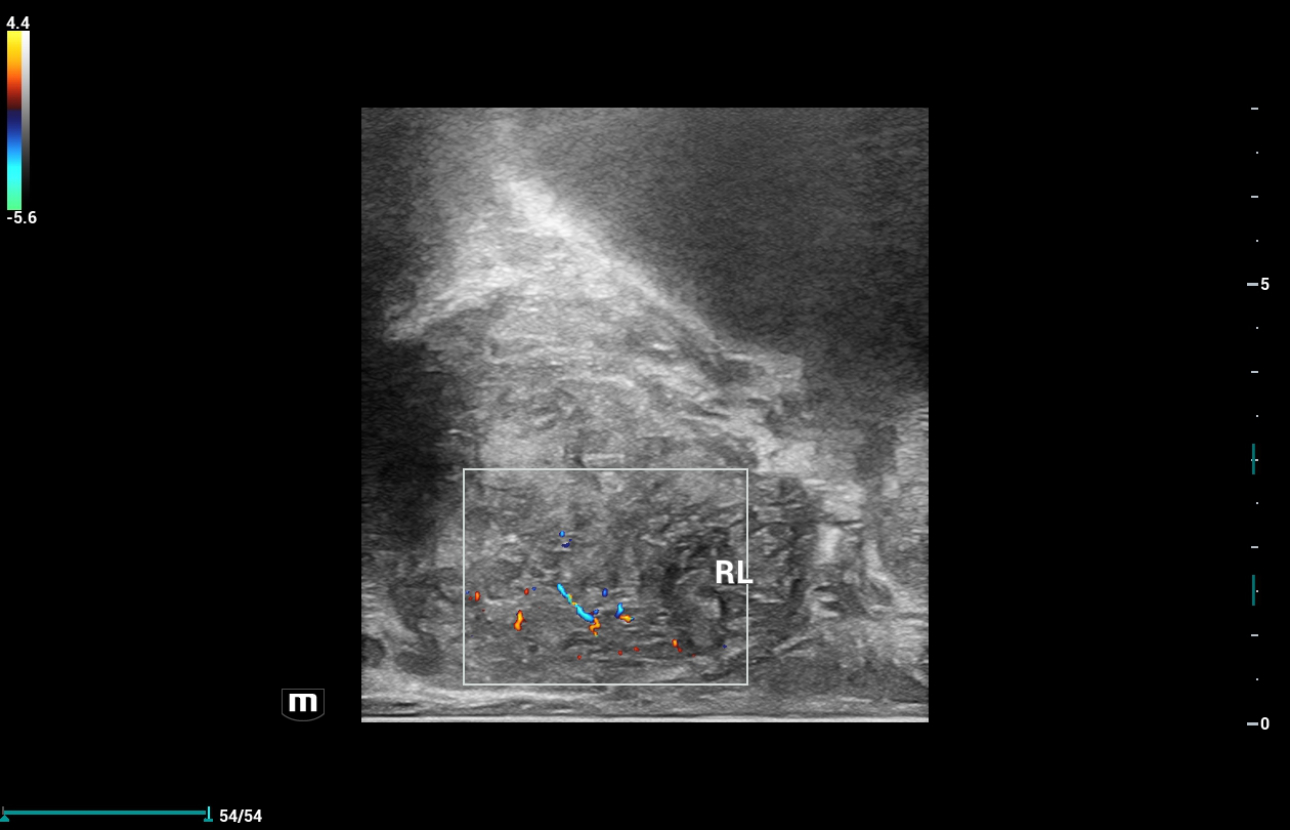

2D and Color Ultrasound findings:

Due to its anatomical location, it is recommended that a prostate ultrasound examination be conducted using real-time transrectal ultrasound (TRUS) with the highest frequency biplane endocavitary transducer (Mindray Resona i9, ELC13-4)

Prostate scanning was performed with a Mindray dedicated biplane convex-linear ultrasound probe. The transducer contains 2 ultrasound probes: the convex array and the linear array. The transverse image of the prostate was obtained with the convex array and the longitudinal image of the prostate was obtained with the linear array. Convex and linear arrays were supported with both Elastography techniques including: Strain Elastography (NTE, Natural Touch Elastography) and 2D Shearwave Elastography (SWE, Sound Touch Elastography).

Ultrasound Findings of rigth lobe of the prostate:

Ultrasound Findings of left lobe of the prostate: